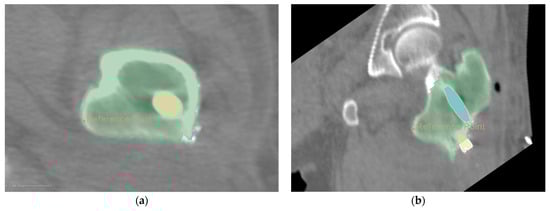

The fixed image and floating image after fine registration are shown in Figure 10. In the two CT images after alignment, the proximal femur parts without the femoral head are overlapped and served as the reference. Observed in 3D space, the proximal pin and distal pin are in the same spatial coordinate system, and after 3D reconstruction, the voxel data of pins in CT are transformed into point cloud data, as shown in Figure 11.

Figure 10.

CT images after registration: (a) fixed images; (b) fine-aligned floating images; (c) the two images in the coordinate system with the overlapping femur as the reference.

Figure 11.

3D point clouds of proximal pins and distal pins in the same spatial coordinate system for both previous and posterior CT images. The purple point cloud is part of the proximal femur and pelvis. The green and blue point clouds represent the proximal and distal pins obtained from the first postoperative CT scan. Gold and red point clouds represent the proximal and distal pins from the second CT image after the previous CT scan, respectively.